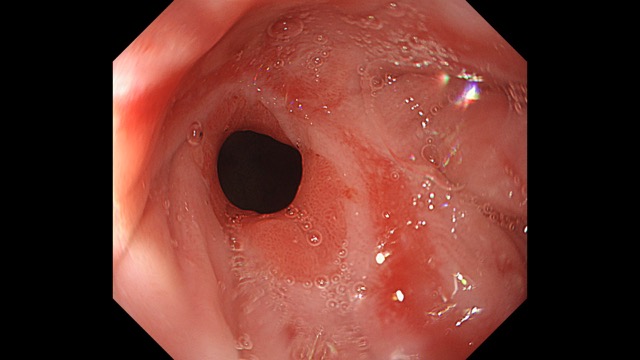

Gastrointestinal Mapping ~Stomach~ 2025.8.27